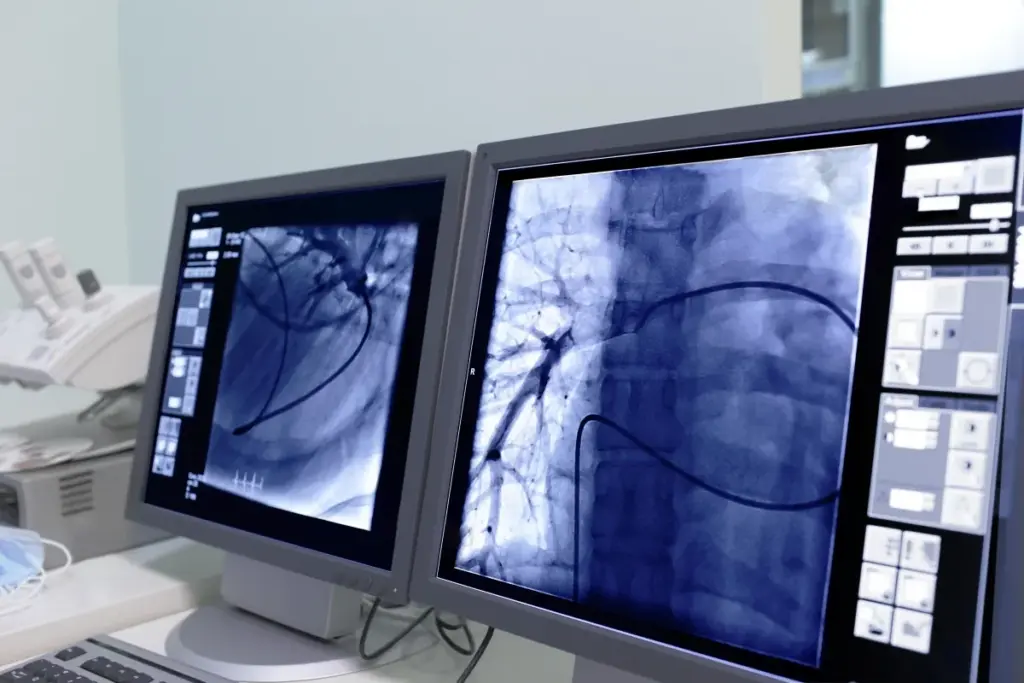

Image-guided procedures are key in interventional radiology. They let our doctors do complex treatments with great accuracy. We use X-ray, ultrasound, and MRI to guide these procedures.

Interventional radiology (IR) is about minimally invasive procedures. These can often replace surgery. Doctors use imaging like x-ray, CT, and ultrasound to guide these procedures.

IR is used in many ways in today’s medicine. It includes vascular procedures, oncologic interventions, and non-surgical treatments for many conditions. Using imaging to guide these procedures helps us make accurate diagnoses and treatments.